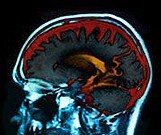

Unique White Matter Injuries for Anxiety, Depression Post TBI

Findings in mild traumatic brain injury patients; no such pattern for irritability